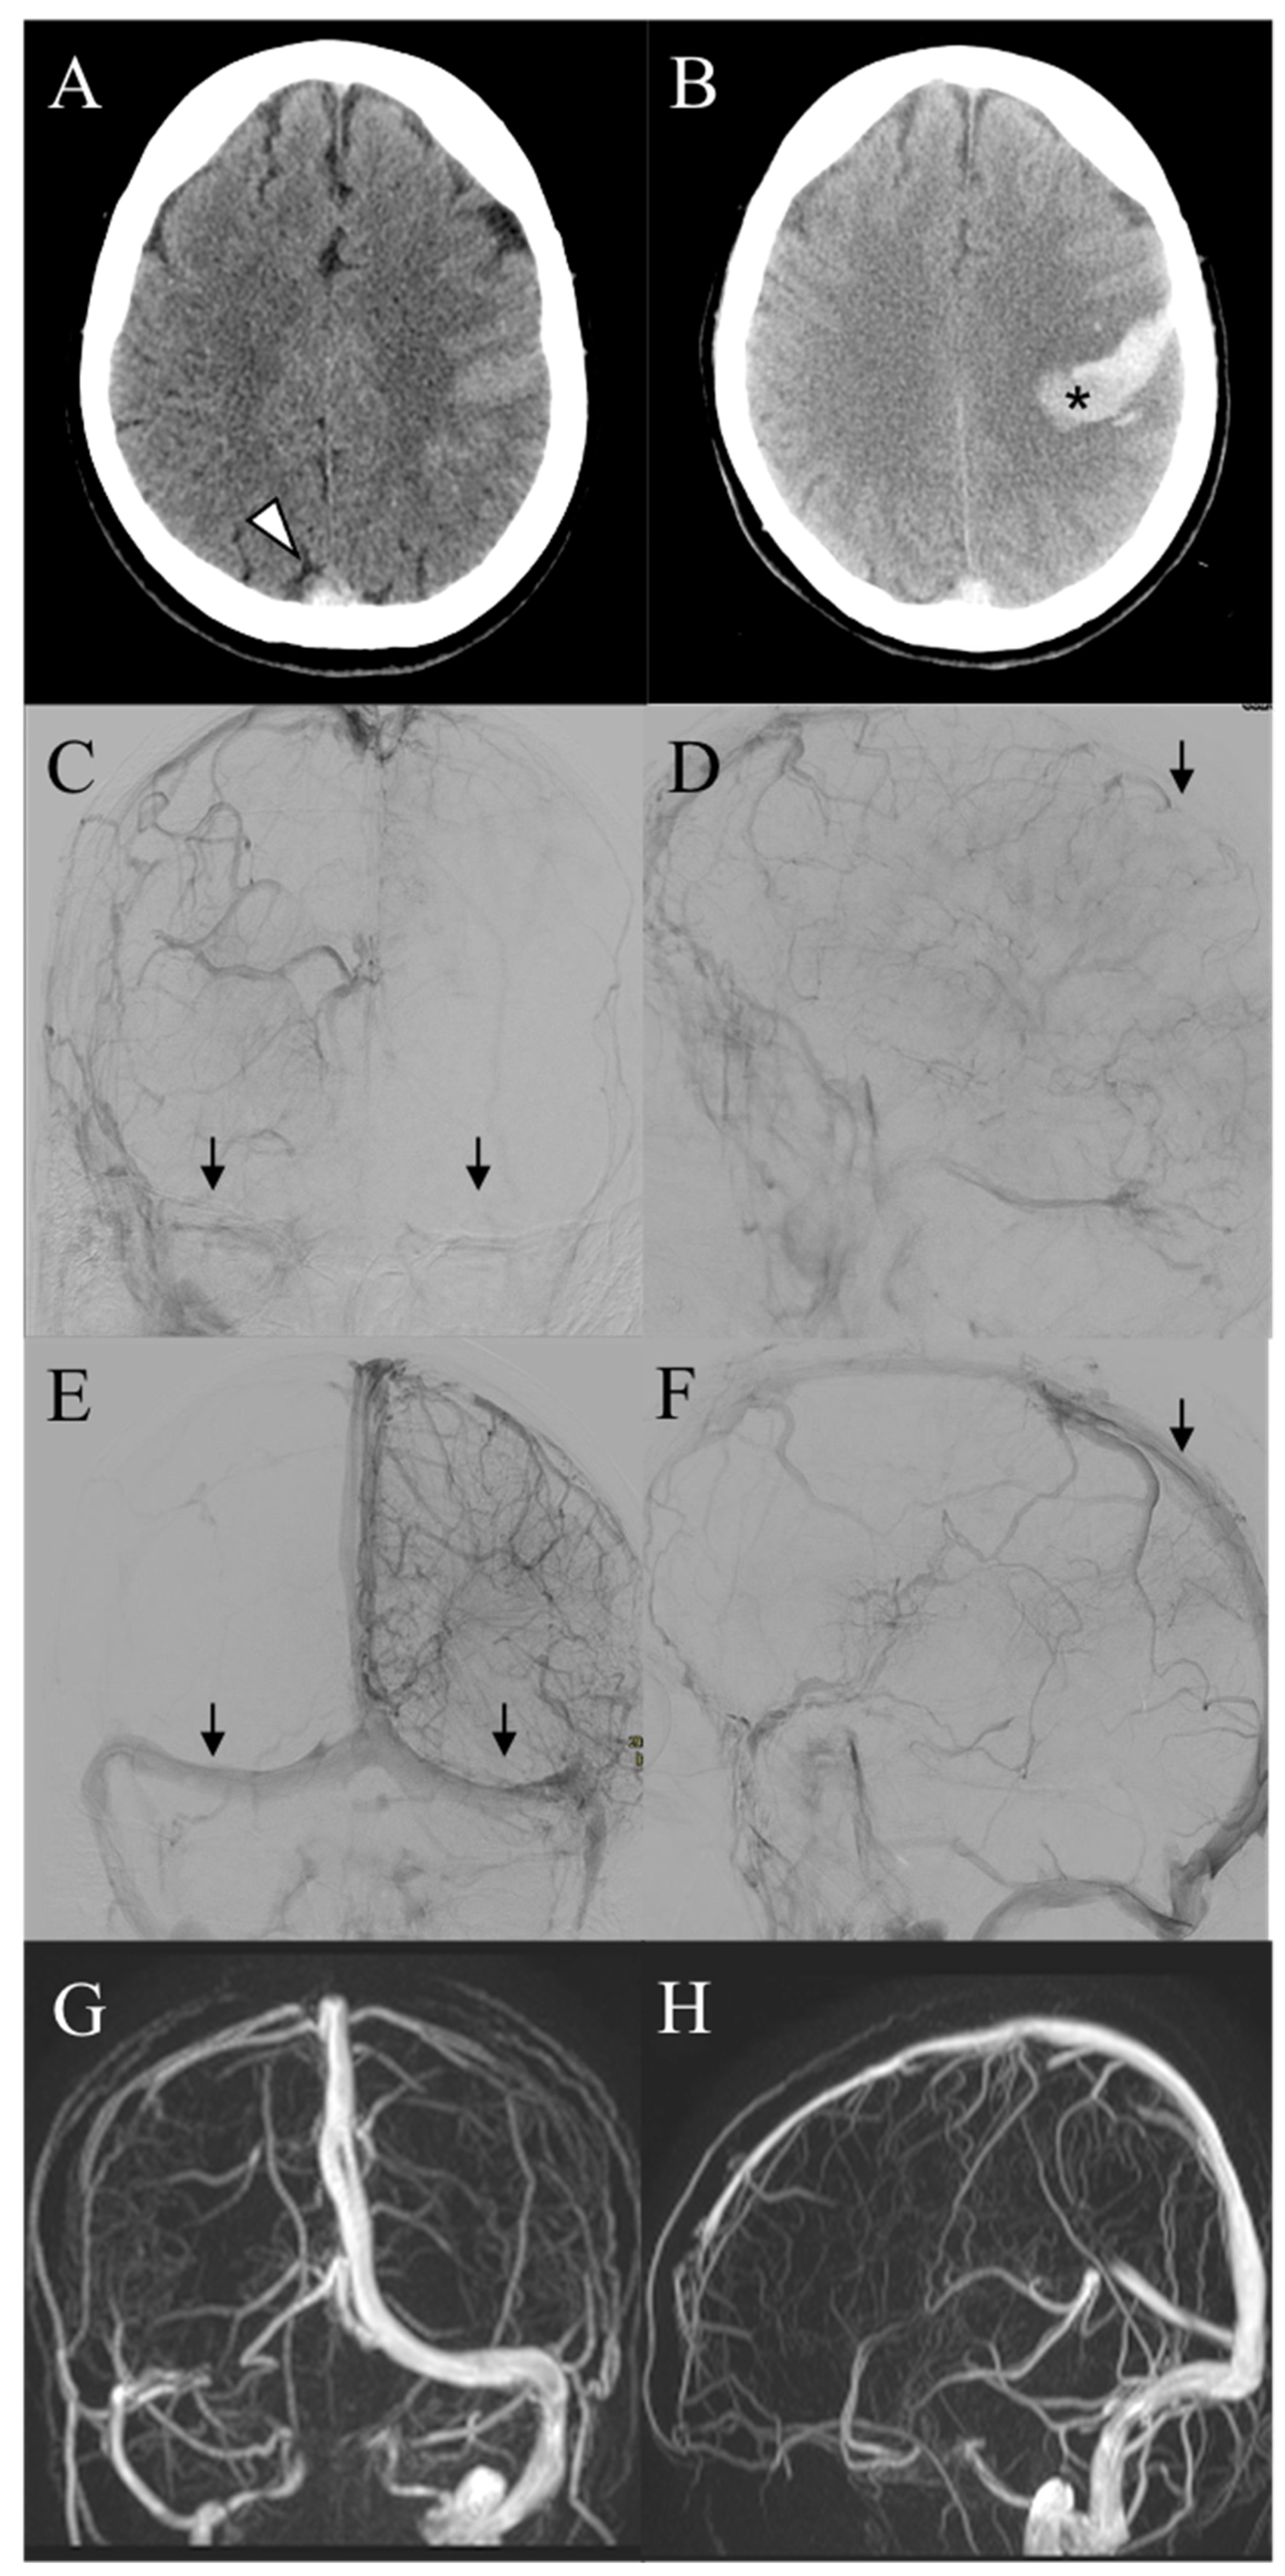

| 1 | F, 72 | Headache, nausea, aphasia, rt hemisyndrome | No identifiable risk | SSS, SS, SrS, TS, VG | SAH | 7 h | Rescue | Combined Aspiration plus Stentriever |

| 2 | F, 84 | Headache, aphasia, rt hemisyndrome | No identifiable risk | TS, ICV, VG, TS, SS | No | 5 h | Primary | Combined Aspiration plus Stentriever |

| 3 | M, 52 | Headache, nausea, dizziness | Antiphospholipid antibodies + | TS | IPH, SAH | 6 h | Primary | Aspiration |

| 4 | F, 51 | Headache, rt hemisyndrome, seizures | Contraceptive pill, MTHFR mutation | SSS | IPH, SAH | 2 h | Primary | Aspiration |

| 5 | F, 40 | Headache, aphasia, seizures | Antithrombine III and Protein S deficiency, contraceptive pill | TS, SS, JV | IPH | 7 h | Rescue | Aspiration |

| 6 | F, 44 | Headache, lt hemisyndrome, seizures | No identifiable risk | SSS | SAH | 1 h | Rescue | Aspiration |

| 7 | M, 41 | Headache, nausea, photophobia, lt sup. arm deficit | ANA+ | SSS | IPH | 2 h | Primary | Combined Aspiration plus Stentriever |

| 8 | F, 44 | Headache, aphasia | Contraceptive pill, activate protein C resistance | TS, SS | SAH | 4 h | Primary | Aspiration |

| 9 | F, 76 | Headache, seizures, loss of consciousness | No identifiable risk | SSS, SrS, TS (both), SS | No | 5 h | Primary | Aspiration |

| 10 | F, 33 | Headache, nausea, lt hemisyndrome | Pregnancy | SSS, SrS, TS (both), SS (both) | No | 2 h | Primary | Combined Aspiration plus Stentriever |

| 11 | F, 49 | Headache, vomiting, dizziness, aphasia, rt hemisyndrome | Recent pulmonary embolism | SSS, TS (both), SrS, | IPH, SAH | 2 h | Primary | Combined Aspiration plus Stentriever |

| 12 | F, 49 | Headache, nausea, dizziness, lt sup. arm deficit | Contraceptive pill, C677T and A1298C MTHFR mutation | Panthrombosis | No | 2 h | Primary | Aspiration |

| 13 | F, 45 | Headache | No identifiable risk | TS, SS | SAH | 6 h | Primary | Aspiration |

| 14 | F, 44 | Headache, nausea, aphasia, rt hemisyndrome | Contraceptive pill | TS | IPH | 3 h | Primary | Combined Aspiration plus Stentriever |

| 15 | M, 83 | Aphasia, rt hemisyndrome | Progestogen therapy | SSS, TS, SS, JV | IPH | 24 h | Rescue | Combined Aspiration plus Stentriever |

| 16 | M, 49 | GCS 9 | Neurosurgery 9 days prior | SSS, TS | No | 5 days | Rescue | Aspiration |

| 17 | F, 16 | Headache, nausea | Previous contralateral CVT, Prothrombin gene mutation | SSS, TS, SS | No | 2 h | Primary | Aspiration |

| 18 | F, 40 | Headache, nausea, rt hemiparesis | Prothrombin gene mutation (A20210G homozygosis) | SSS, SrS, TS (both), SS | IPH | 48 h | Rescue | Aspiration |

| 19 | F, 27 | Headache, nausea, dizziness, lt hemisyndrome | Contraceptive pill | SSS, rt parietal vein | IPH | 48 h | Rescue | Combined Aspiration plus Stentriever |

| 20 | F, 27 | Headache, nausea, rt hemisyndrome | Thalassemia | SSS, lt temporal vein | IPH | 48 h | Rescue | Combined Aspiration plus Stentriever |

| 21 | M, 19 | Headache, nausea, vomiting, dizziness | Active protein C resistance, MTHFR mutation | TS, SS | IPH, SAH | 3 h | Primary | Aspiration |